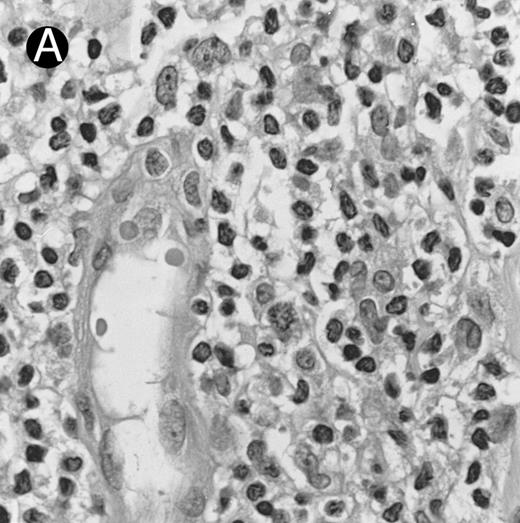

Fig. 3.

Cutaneous nasal-type NK/T-cell lymphoma (case no. 34). (A) This biopsy was initially misinterpreted as vasculitic lesion because of the small size of the lymphoid cells and the minimal cellular atypia. (B) Large numbers of lymphoid cells in the skin show positive labeling for EBERs on in situ hybridization. The sweat gland in the left field is negative.

By definition, the neoplastic cells showed CD56 expression (Fig 4). All except 2 cases (cases no. 7 and 12) reacted with the polyclonal CD3ε antibody on paraffin sections, but both CD3ε cases were immunoreactive for CD43 and CD45RO. Among 18 cases in which frozen tissue was available for analysis, all were CD2+; 1 case each stained for CD3/Leu4 (weak staining), CD7, and CD8 and all cases were negative for CD4, CD5, CD16, CD57, and B-lineage markers. Thirty-two (94.1%) cases showed labeling for EBERs in practically all neoplastic cells (Fig 3B); 2 cases were negative.